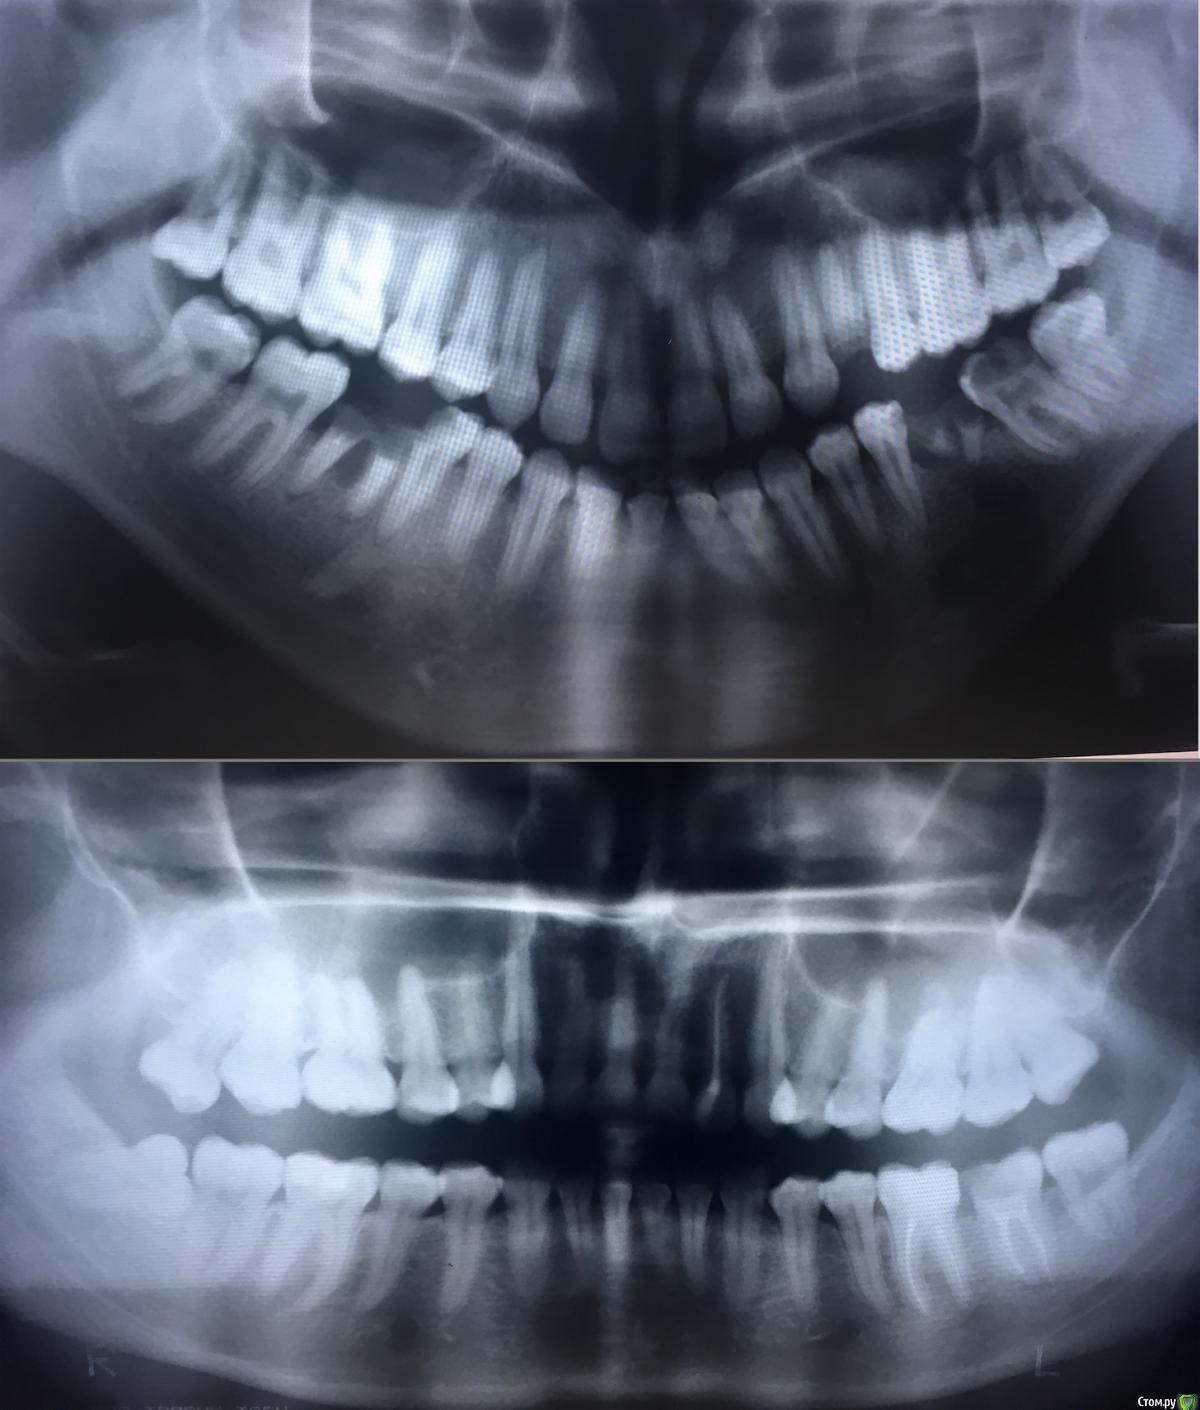

MRZ Опубликовано 1 июля, 2018 Поделиться Опубликовано 1 июля, 2018 Здравствуйте. Подскажите, пожалуйста, являются ли верхние восьмерки ретинированными и дистопированными? Ссылка на комментарий

MRZ Опубликовано 1 июля, 2018 Автор Поделиться Опубликовано 1 июля, 2018 Чьи эти снимки?Homo sapiens )) Мужчина 30 летЖенщина 30 лет 2 Ссылка на комментарий

MRZ Опубликовано 1 июля, 2018 Автор Поделиться Опубликовано 1 июля, 2018 с какой целью интересуетесь Назначено удаление. В плане указано как "удаление ретенированного, дистопированного зуба сложное" Сложное удаление дороже простого. Погуглив эти непонятные мне слова, разобраться не получилось. На мой непрофессиональный взгляд ретенированный, дистопированный зуб - нижняя восьмерка справа, на нижнем снимке. А не верхние зубы мудрости Помогите, пожалуйста, разобраться. 1 Ссылка на комментарий

MRZ Опубликовано 1 июля, 2018 Автор Поделиться Опубликовано 1 июля, 2018 почему бы не задать вопрос своему врачу? Какой из двух снимков Ваш? да, обязательно задам когда в следующий раз увижусь в день удаления. Мой нижний. Верхний супруга. Ссылка на комментарий

red_butler Опубликовано 1 июля, 2018 Поделиться Опубликовано 1 июля, 2018 третьи моляры на верхней челюсти, на обоих снимках не ретенированные. На втором снимки дистопированы Ссылка на комментарий